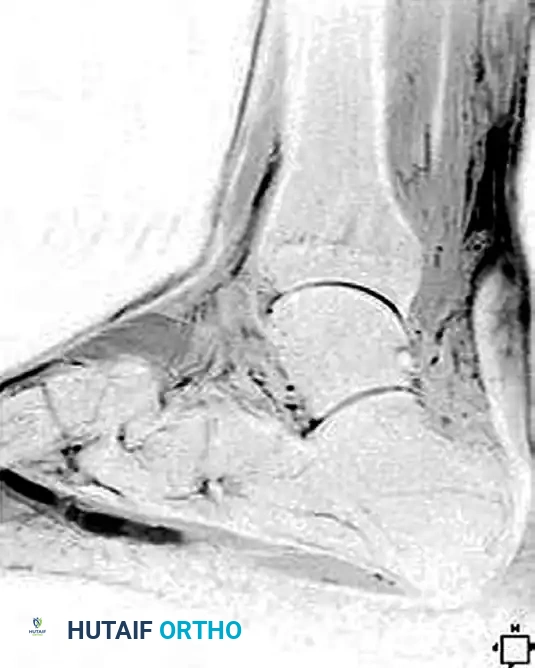

Imaging Evaluation

Magnetic Resonance Imaging (MRI) is the gold standard for evaluating chronic ruptures. It is highly helpful in estimating the exact gap between the retracted, degenerated ends of the tendon, which dictates the surgical reconstructive algorithm. Chronic ruptures appear as an area of low-intensity signal on T1-weighted images and exhibit an alteration in T2-weighted signal due to scar interposition and tendinosis.

Image